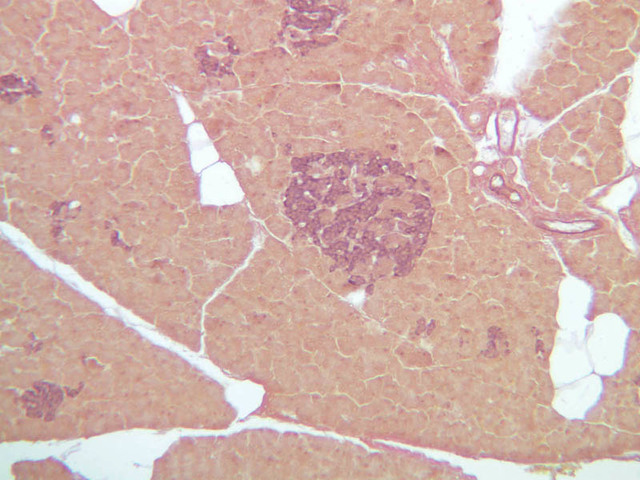

Scan slide B-36 (H&E [10x, 20x] [10x, 20x). Note that in this H&E preparation most of the pancreas consists of rather compactly arranged, darkly stained cells. The compact, darkly stained regions constitute the exocrine portion of the pancreas. (Of what organ does the exocrine pancreas remind you?) The endocrine portions of the pancreas consist of small bits, or islands, of more lightly stained tissue that is somewhat irregularly dispersed within the substance of the exocrine pancreas. Drawing on the name of their discoverer, the endocrine portions of the pancreas are known as the islets of Langerhans.

Endocrine pancreas

Although H & E staining permits ready identification of the islets of Langerhans, it does not permit differentiation of the various cell types that comprise the islets (B-36, H&E [10x, 20x, 40x-labeled]). There are no slides in the class collection that permit identification of all of the cell types of the endocrine pancreas. However, the sections on slides B-37 and B-40 permit specific identification of two cell types. Slide B-37 has been stained by the aldehyde fuchsin technique, which lends a magenta coloration to the granules of the insulin-producing B-cells. All other cells in the islets stain a dirty orange color (B-37 [10x, 20x, 40x] [10x, 20x, 40x]). Most of these orange-colored cells are the glucagon-secreting A-cells; however, you should bear in mind that somatostatin-secreting D-cells, as well as APUD cells that secrete pancreatic polypeptide are also scattered about the islet. The section on slide B-40 has been prepared by a silver impregnation method that renders some of the APUD cells in the islets (which appear as “clear cells” in ordinary preparations) dark brown or black (B-40 [10x, 20x, 40x]).